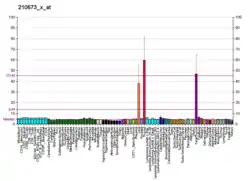

For lung cancers, adenocarcinomas are usually positive, while squamous cell carcinomas and large cell carcinomas are rarely positive. Small cell carcinomas (of any primary site) are usually positive. TTF1 is more than merely a clinical marker of lung adenocarcinoma. It plays an active role in sustaining lung cancer cells in view of the experimental observation that it is mutated in lung cancer.[11][12][13][14]

However others have found that TTF-1 staining is often positive in pulmonary adenocarcinomas, large cell carcinomas, small-cell lung carcinomas, neuroendocrine tumors other than small-cell lung carcinomas and extrapulmonary small-cell carcinomas.[16]

- ↑ Image by Mikael Häggström, MD. Source for significance: Bejarano PA, Mousavi F (2003). "Incidence and significance of cytoplasmic thyroid transcription factor-1 immunoreactivity". Arch Pathol Lab Med. 127 (2): 193–5. doi:10.5858/2003-127-193-IASOCT. PMID 12562233.